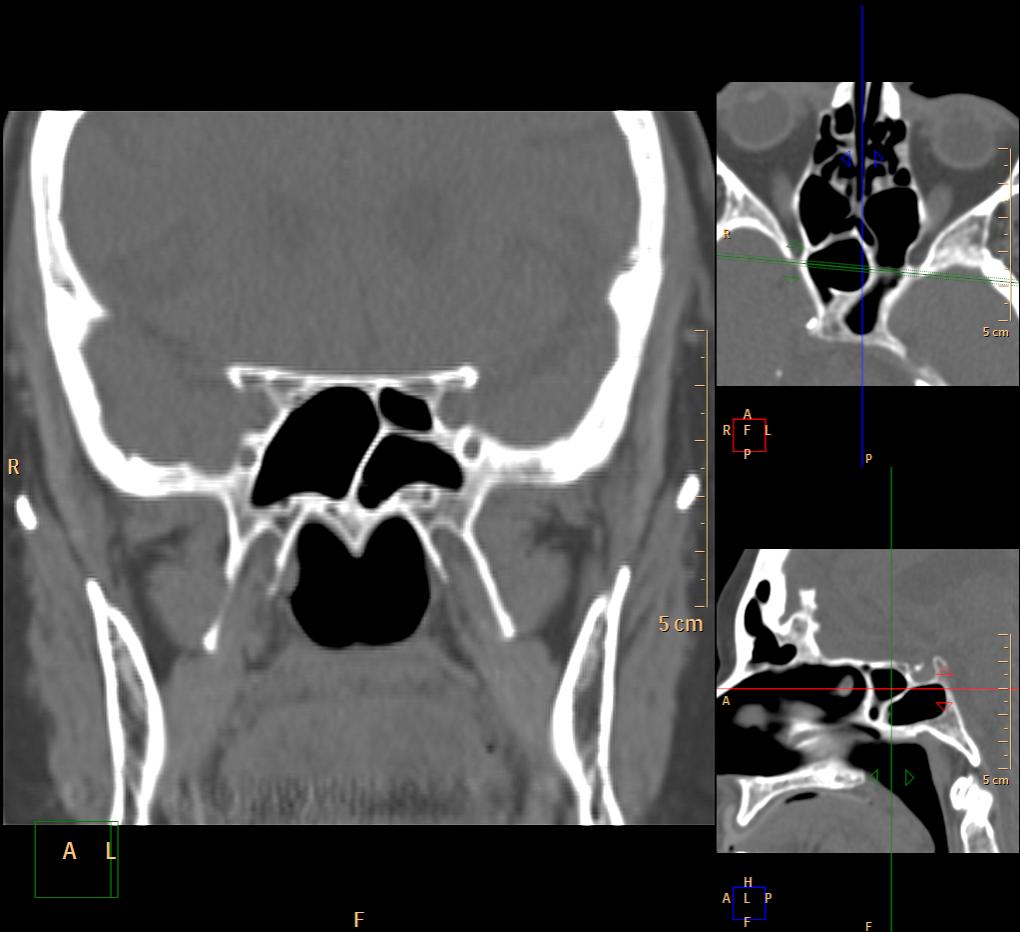

Одна пазуха: